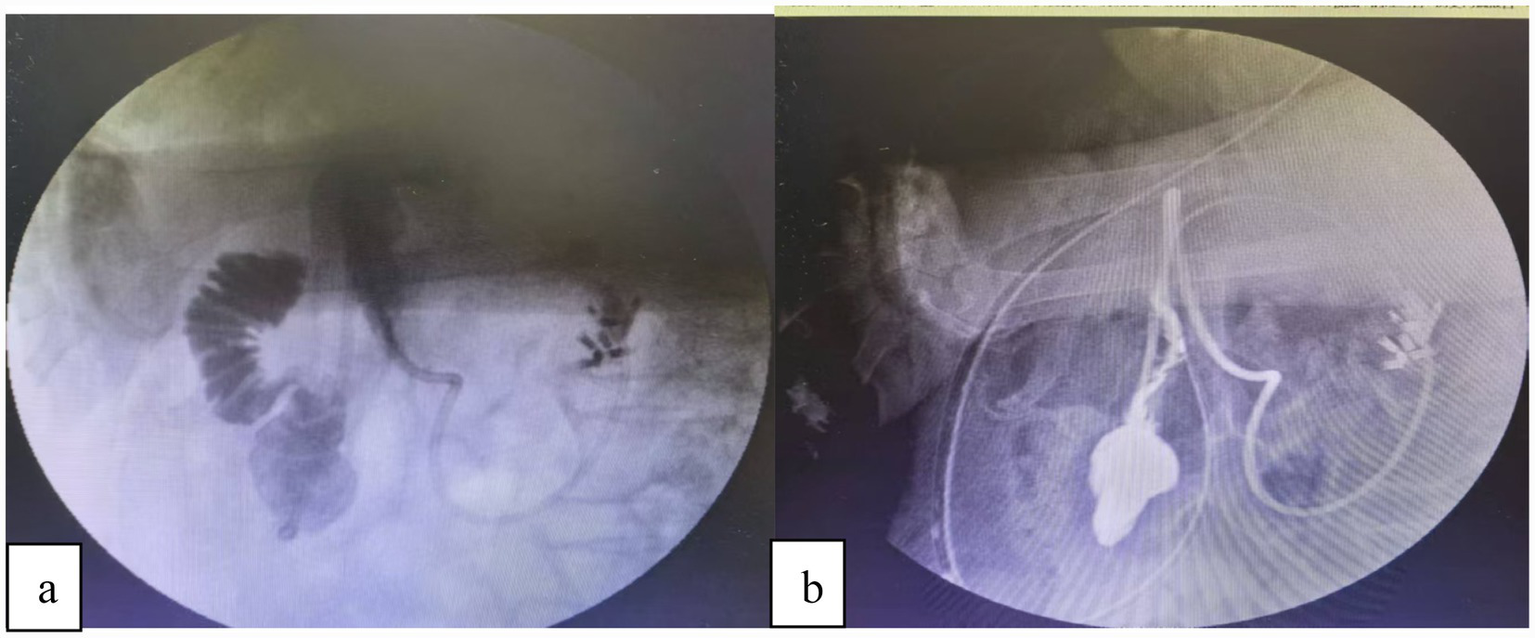

Case 2: upper endoscopy showed a pedunculated polypoid lesion adjacent to the papilla, with biopsy confirming high-grade dysplasia. The CT scan was normal. During the scheduled EUS to assess the relationship of the lesion to the papilla, a perforation occurred on the contralateral side of the papilla (Figure 1).

Figure 1

(a) Following an EUS examination, a perforation was identified in the posterior duodenal wall. We used a therapeutic endoscope (with a 3.2 mm channel) equipped with a transparent cap and connected to a carbon dioxide insufflation system. This provided optimal visualization and full exposure of the entire perforation site. (b) After multidisciplinary discussions with the anesthesia and surgical teams at the Digestive Endoscopy Center, we proceeded to directly use endoscopic clips to perform purse-string closure of the perforation.